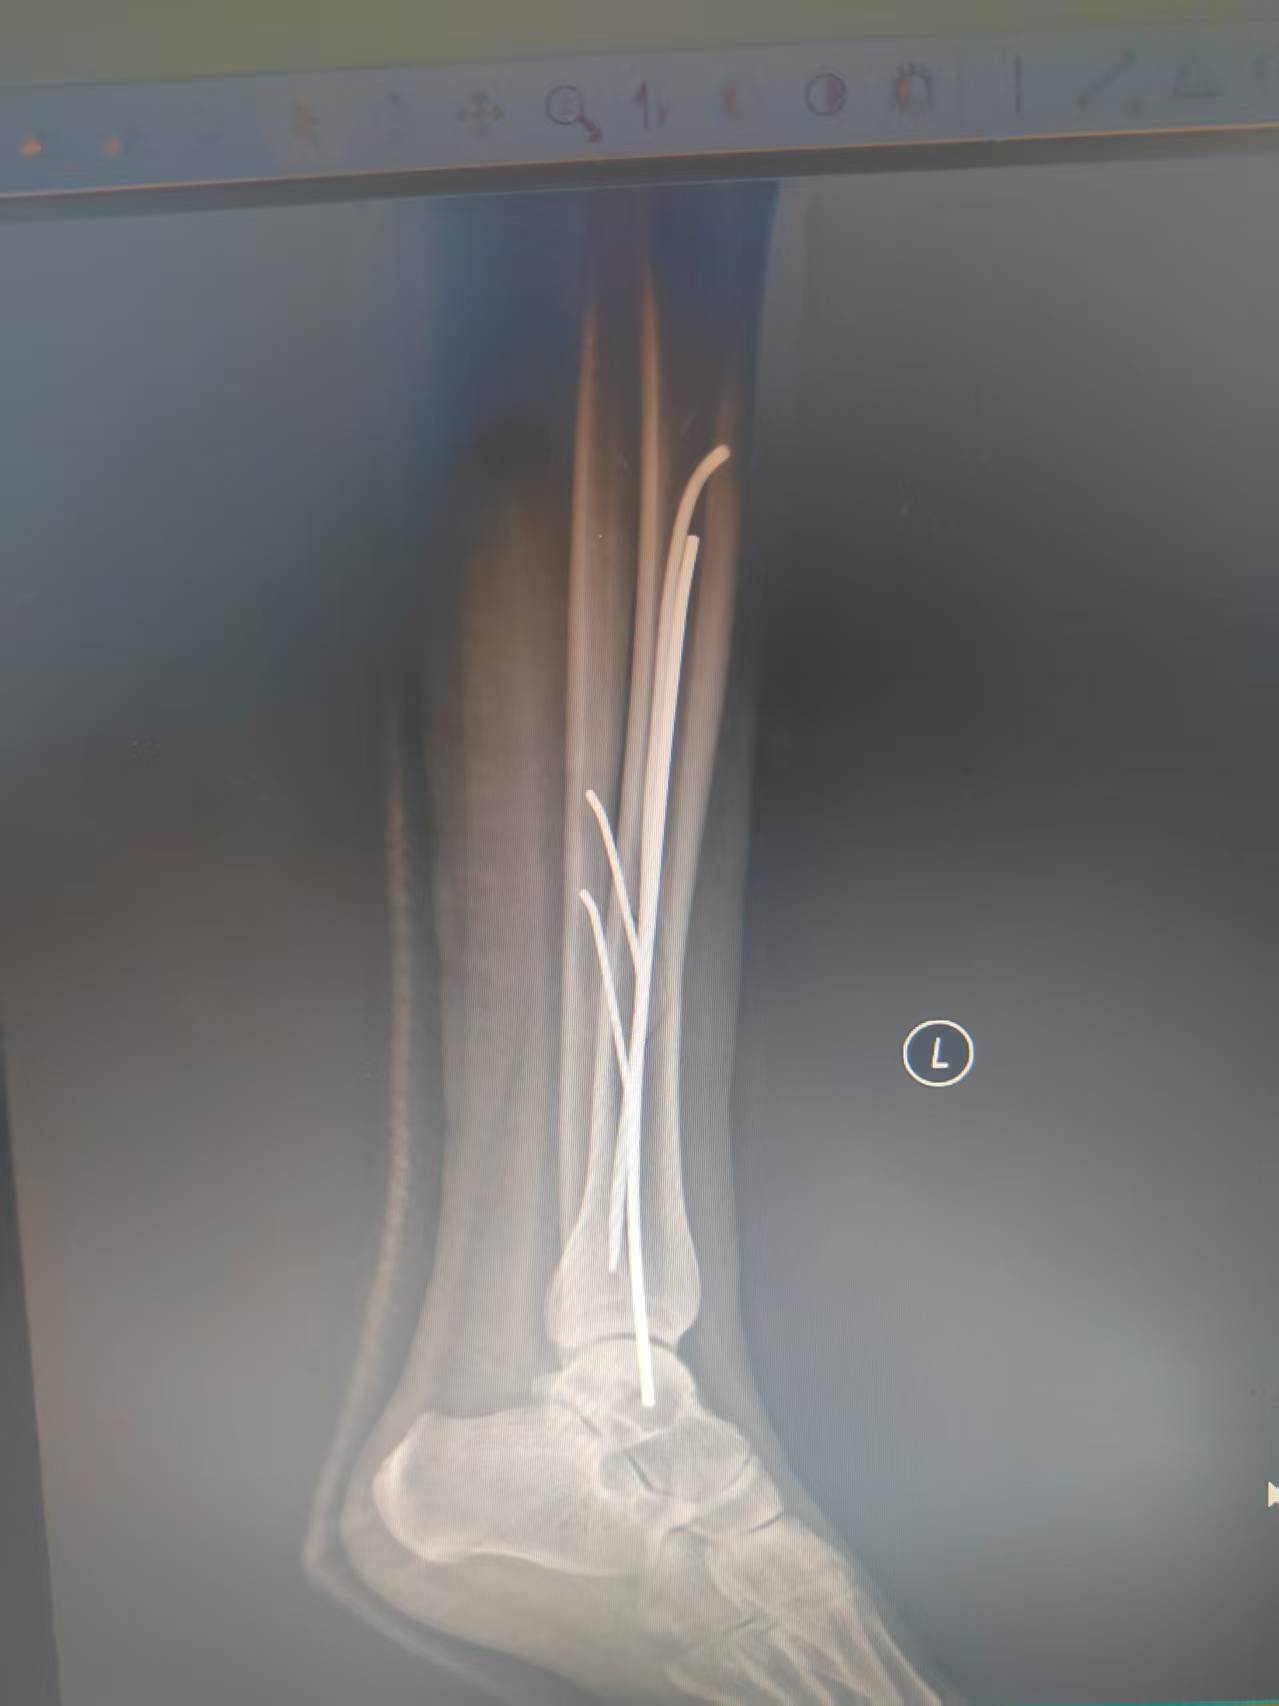

伤后第三天,通过他人介绍,为了少留疤痕,艾女士克服种种困难,忍痛赶来河南洛阳,找到我院洛阳院区手法正骨(微创正骨)二科主诊医师薛继强。薛继强接诊后,完善术前检查,排除下肢深静脉血栓等手术禁忌症后,为其量身定制了“经皮钳夹复位闭合穿针固定术”,手术用时半小时左右,利用付氏钳、点式复位钳纠正骨折位移,达到了解剖复位,利用克氏针和弹性髓内针进行稳固支撑与防旋转固定,确保骨折部位稳定,皮肤上仅有几个针眼,满足了患者和家人的愿望。